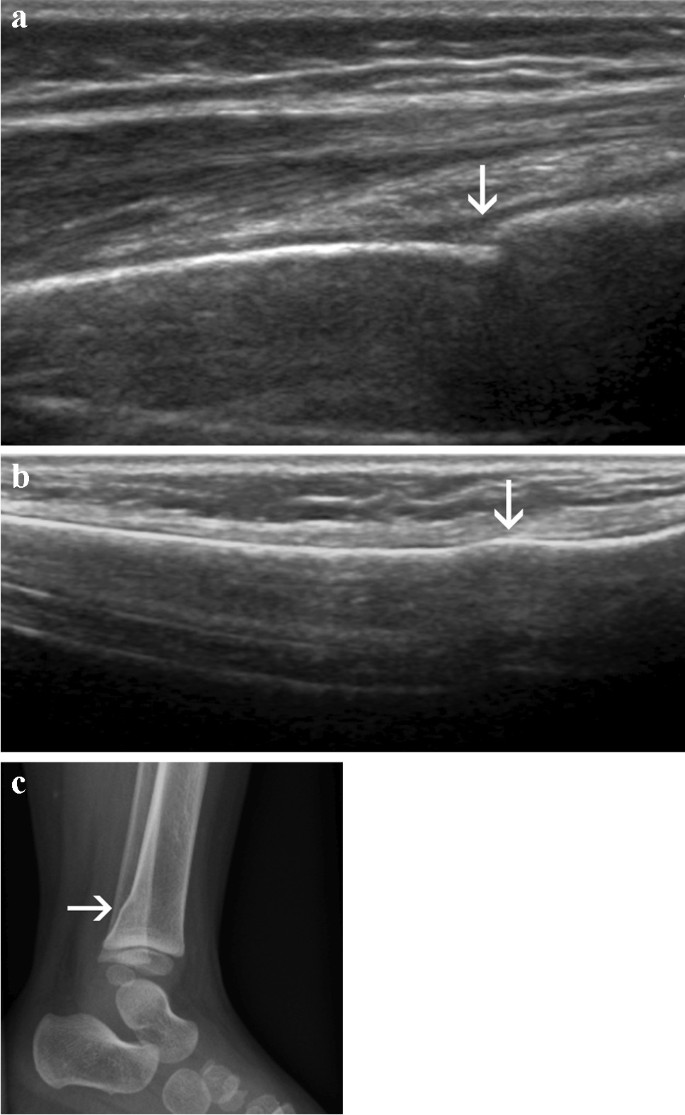

ultrasound: cortical bone

Hyperechoic (bright) linear line with posterior acoustic shadowing due to complete reflect

ultrasound: tendon

comprise multiple individual, longitudinally oriented, parallel collagen fibers that are tightly bundled, resulting in a fibrillary pattern on ultrasound

This results in the characteristic hyperechoic appearance of tendons when the US beam is oriented 90 degrees to the tendon